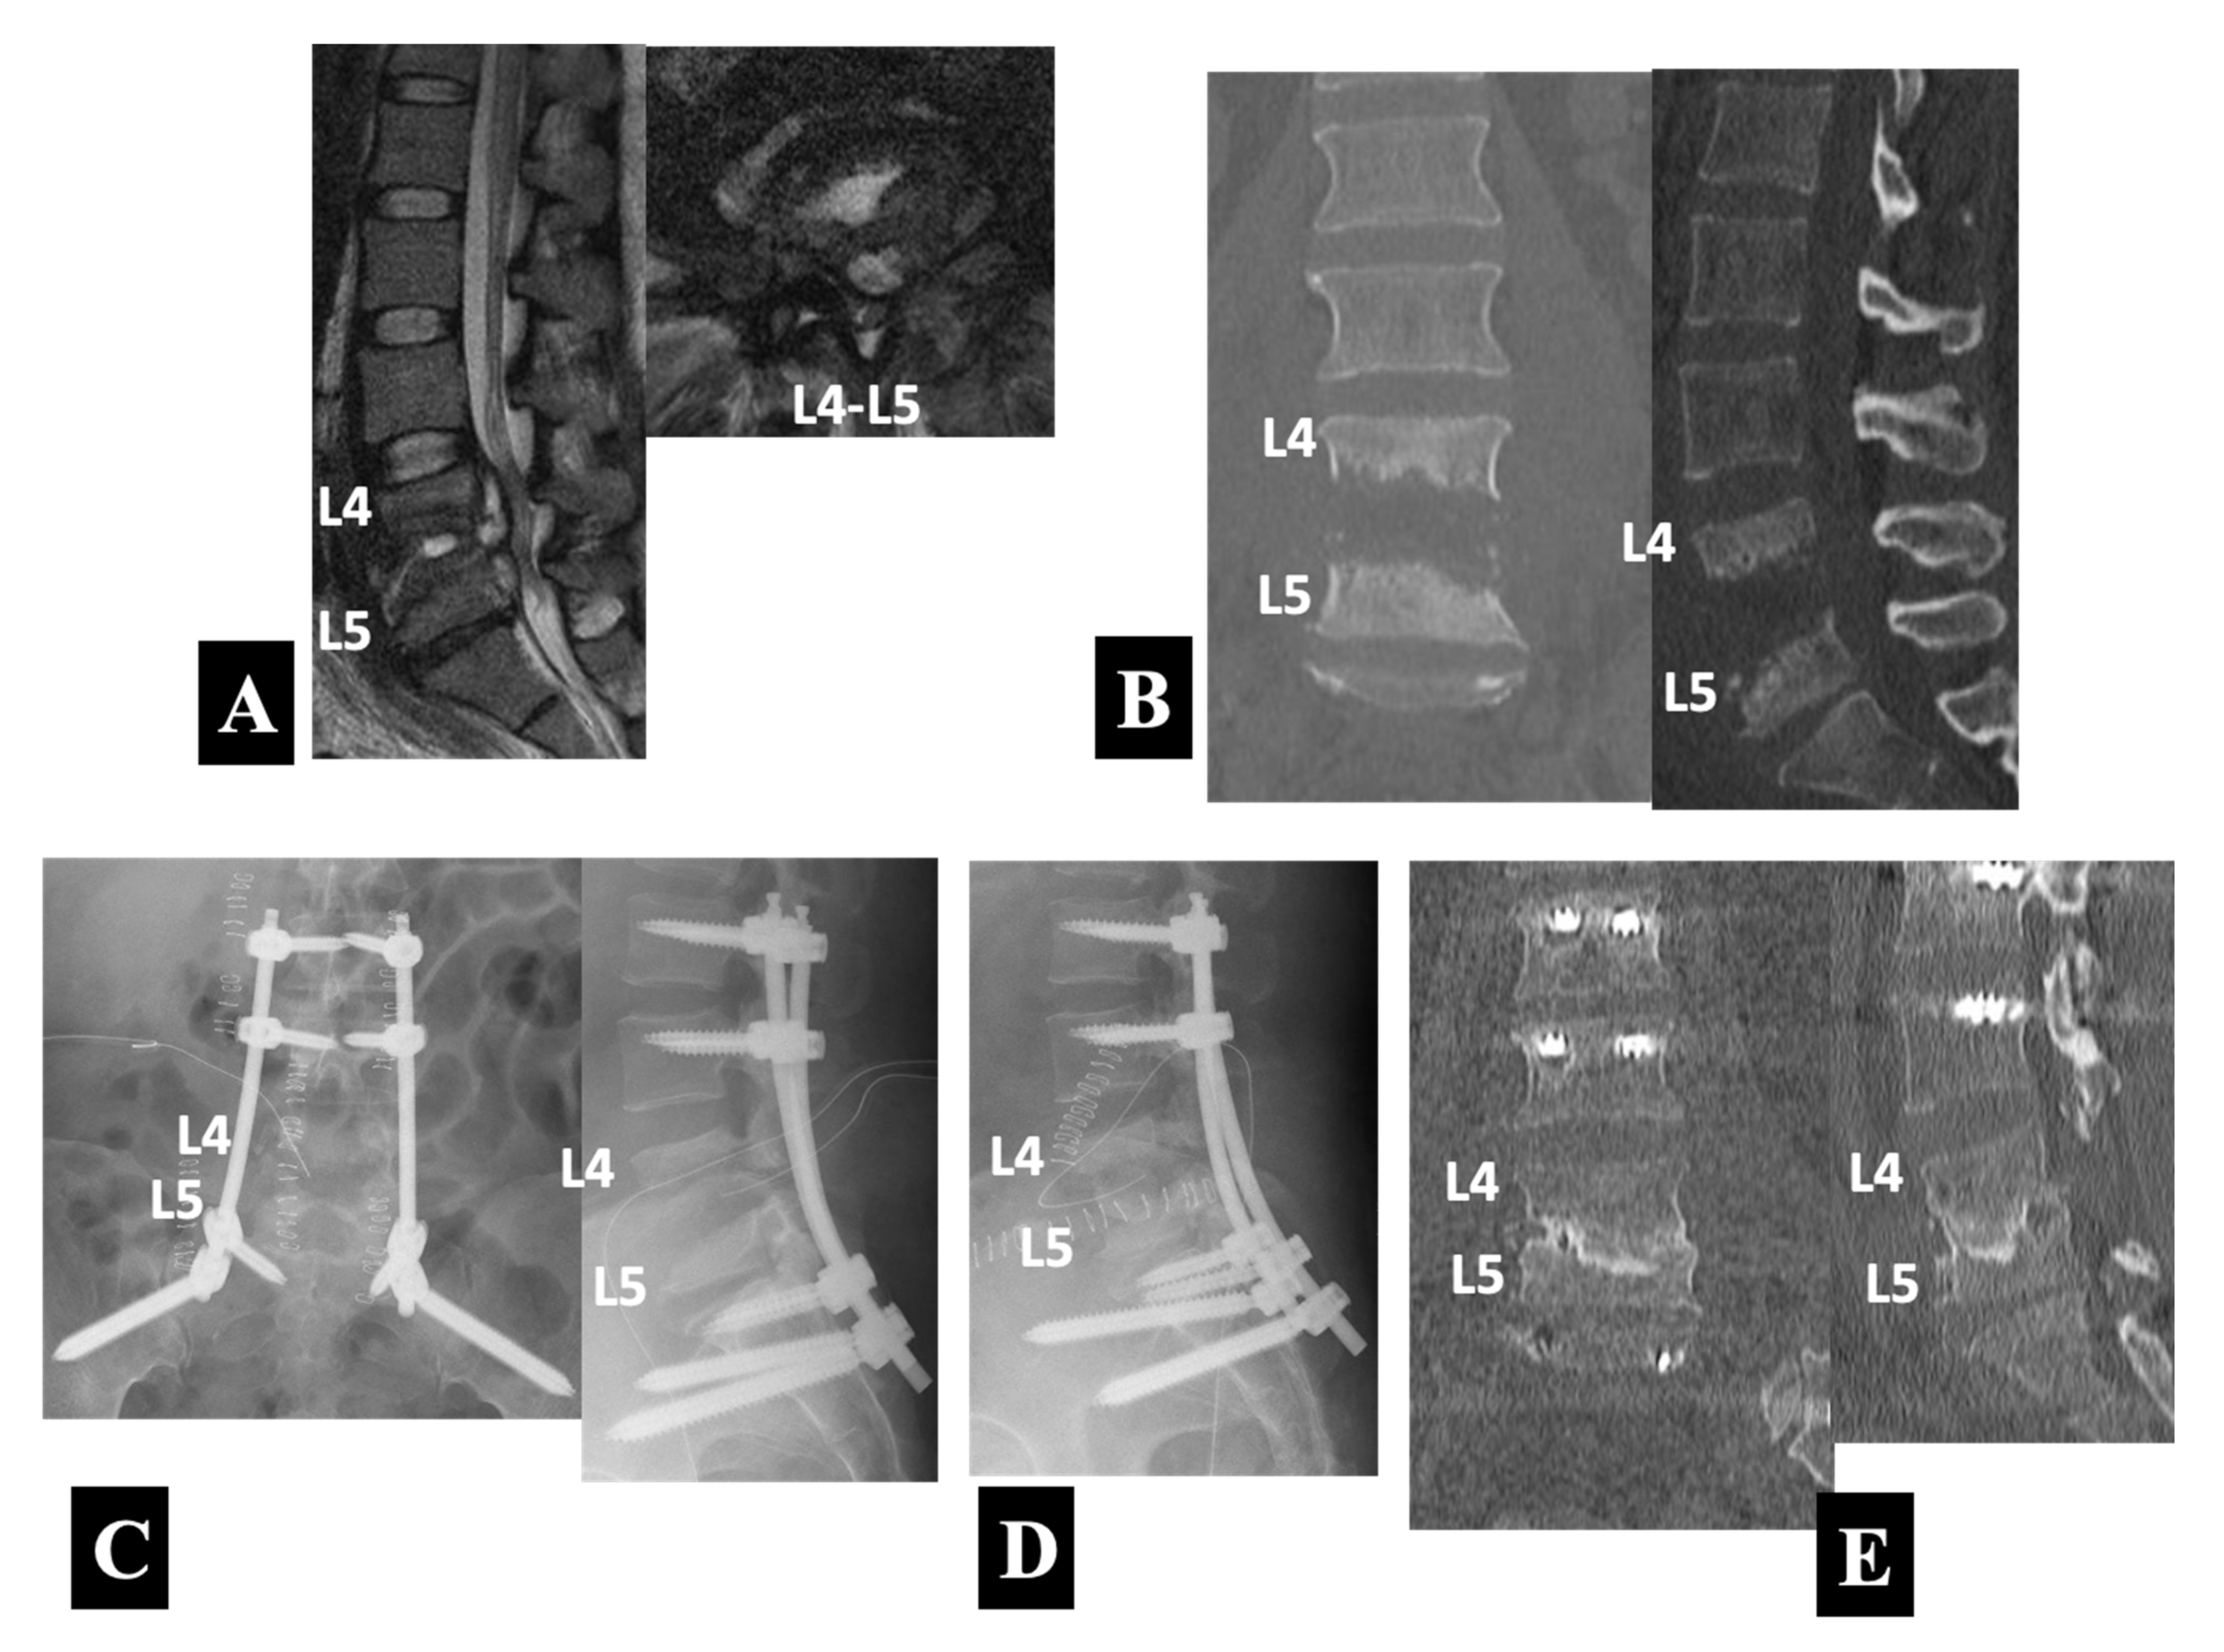

- Case 3 in Group 2-B (Figure 5):